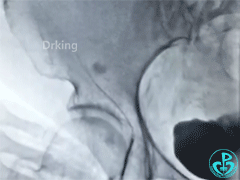

股动脉造影:

泥鳅导丝怎么用泥鳅导丝又惹祸,股动脉分支破裂要堵上!_https://www.jmylbn.com_新闻资讯_第3张

泥鳅导丝怎么用泥鳅导丝又惹祸,股动脉分支破裂要堵上!_https://www.jmylbn.com_新闻资讯_第4张